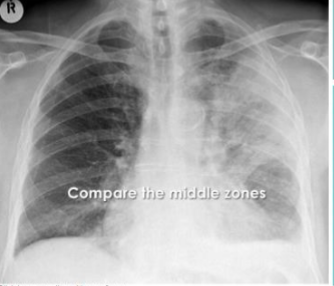

What are these silhouette signs? what causes them?

1: L Heart boarder (lingula disease), 2: Hemidiaphragm (lower lobe lung disease), 3: paratracheal stripe (paratracheal disease), 4: chest wall (lung, pleural or rib disease)

5: aortic knuckle (anterior mediastinal or L upper lobe disease), 6: paraspinal line (post thorax disease), 7: R heart boarder (middle lobe disease) 8: density above horizontal fissure